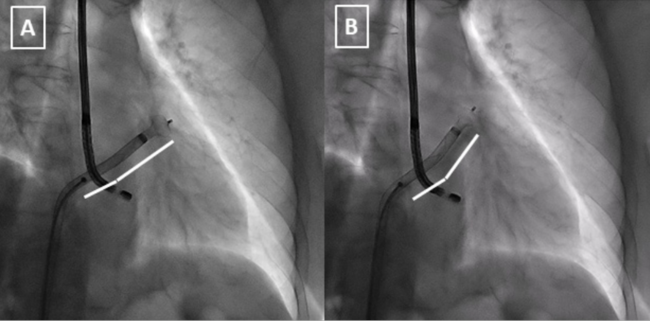

In this case, although we faced classical chicken-wing anatomy, it was difficult to achieve a coaxial angle, as we can appreciate in computed tomography and fluoroscopy during the first attempt with the conventional 45º x 45º sheath (Figures 2A, 2B). Using the steerable sheath, even with a posterior-inferior transseptal puncture, the angle was again not desirable (Figures 2C-2F). Therefore, with a slight deflection (red arrow), the coaxiality improved in a determinant way. These small variations must be done in the ball position to prevent complications. These corrections offer the possibility to achieve an optimal angle for the deployment (white lines in Figures 3A, 3B; Video Series), helping to complete the desired final position (Figure 3C).